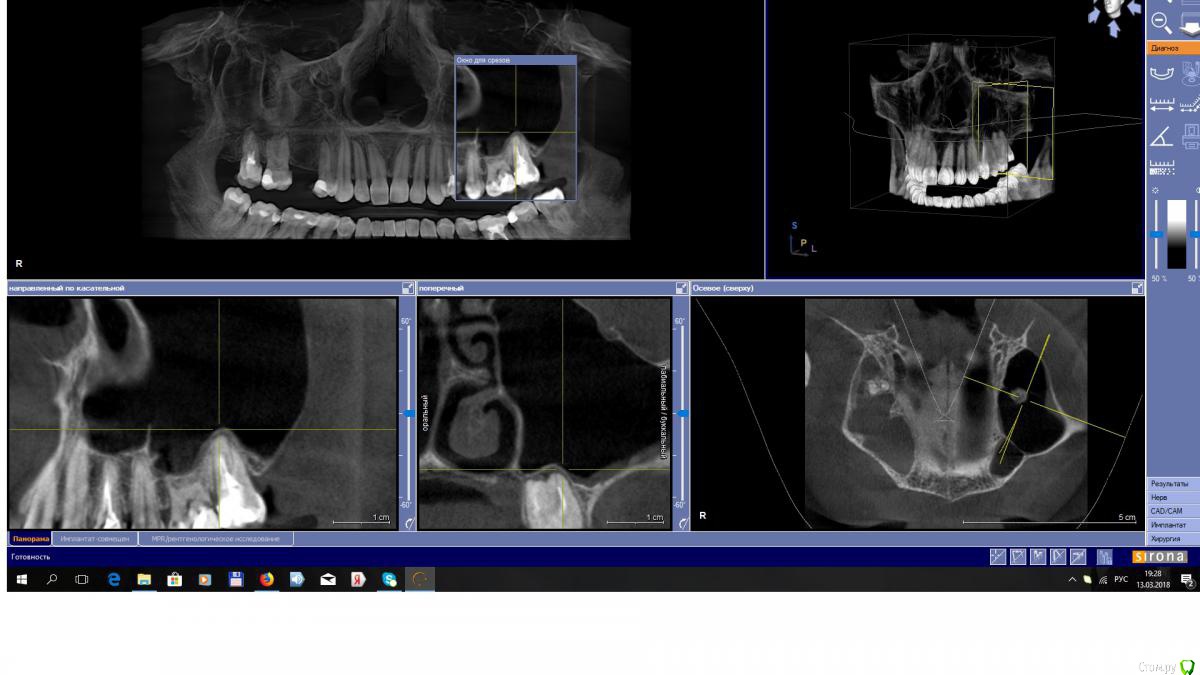

EEcho Опубликовано 7 марта, 2018 Поделиться Опубликовано 7 марта, 2018 Доброго времени суток. 3 месяца назад пациентка обратилась с целью поставить имплант в области 15.На КТ нарисовалась такая картинка, инородное тело и возможен гайморит без жалоб. была направлена к ЛОР. ЛОР сделал ревизию.прошло 2 месяца , сделали повторный КТ и сейчас картина такая. Что делать, ждать или отправить опять к ЛОР, или что-то можно уже делать? Ссылка на комментарий

EEcho Опубликовано 13 марта, 2018 Автор Поделиться Опубликовано 13 марта, 2018 Я то же сначала подумал о 16, но ЭОД показала норму, 17 резорциненый уже много лет и без изменений в апикальных тканях.снимки противоположной пазухи прилагаю. Про грибы как то не подумал, с ними ни разу не сталкивался, Спасибо!!! Ссылка на комментарий